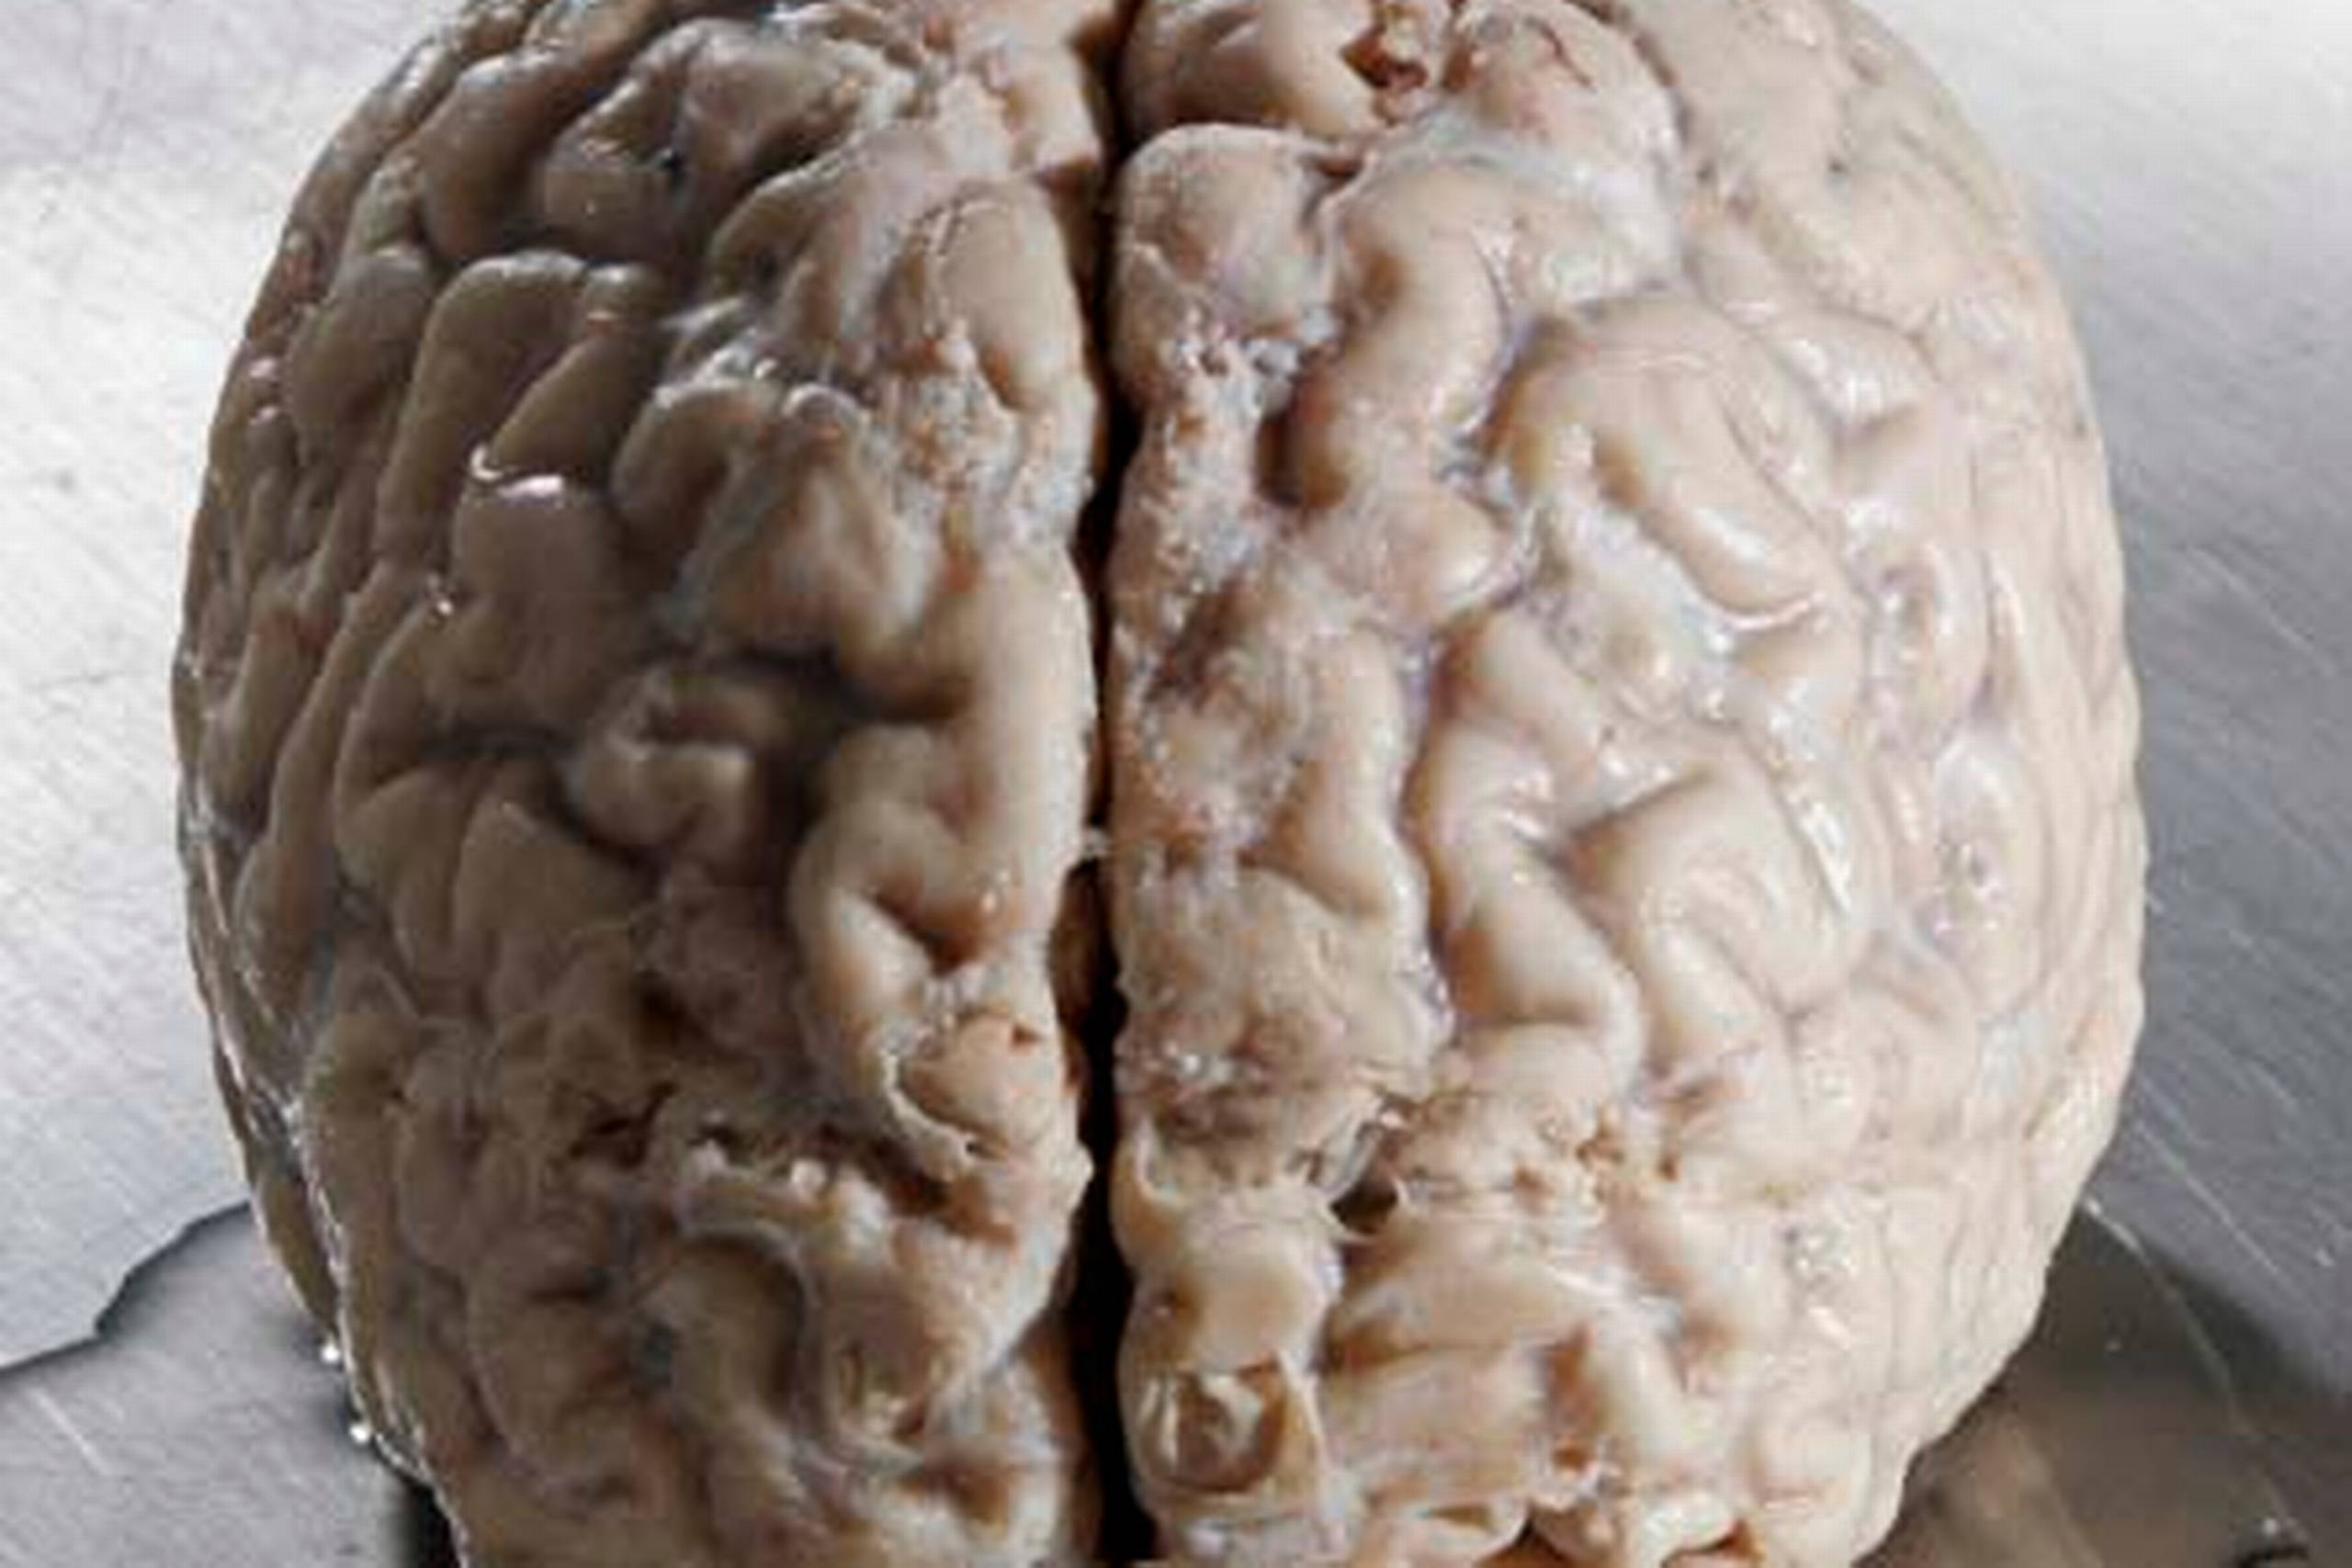

34. Frøhjerter og hjernekemi